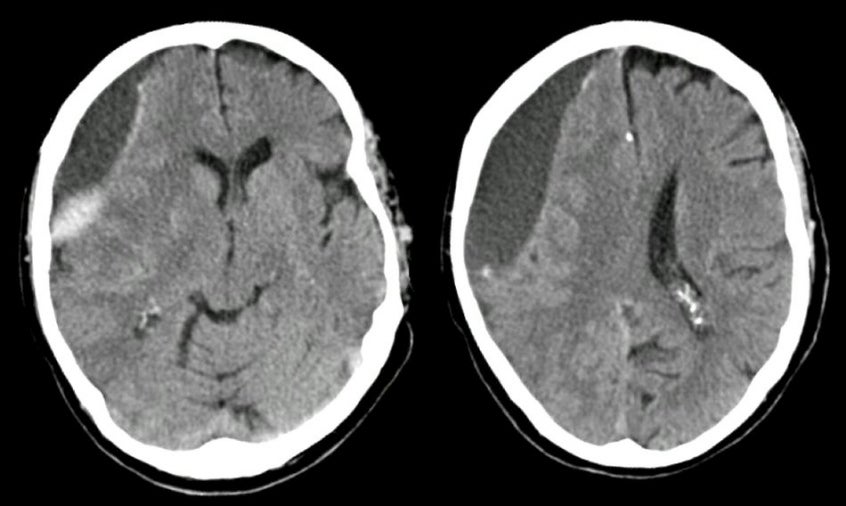

Медицинские аспекты и диагностика субдуральной гигромы мозга